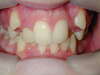

Malpositions incisives

Incisives en avant et écartées

Malpositions des canines.

Recouvrement incisif excessif